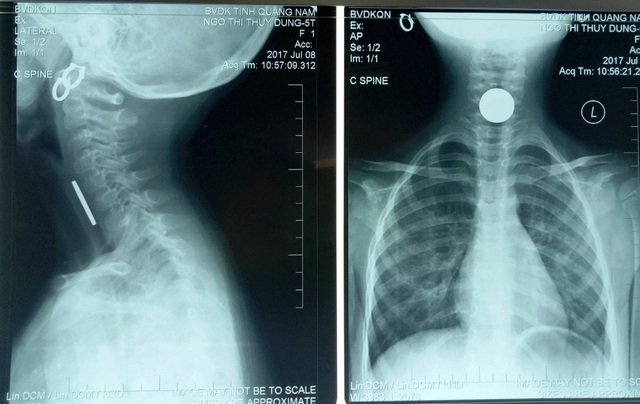

Kết quả chụp X-Quang, các các bác sĩ phát hiện có dị vật cản quang nằm ở vùng cổ bệnh nhân, cháu Vy được chuyển ngay lên Khoa Gây mê hồi sức để gắp dị vật.

Bác sĩ Trần Giám, Trưởng Khoa Tai mũi họng - người trực tiếp soi cho cháu bé cho biết, dị vật nằm ở đốt cổ thứ 6 và khi lấy ra là một đồng xu mệnh giá 500 đồng Việt Nam với đường kính 22mm.